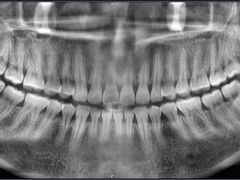

• 岳辰齿科(浦东长泰店)

• -岳辰齿科(浦东长泰店)